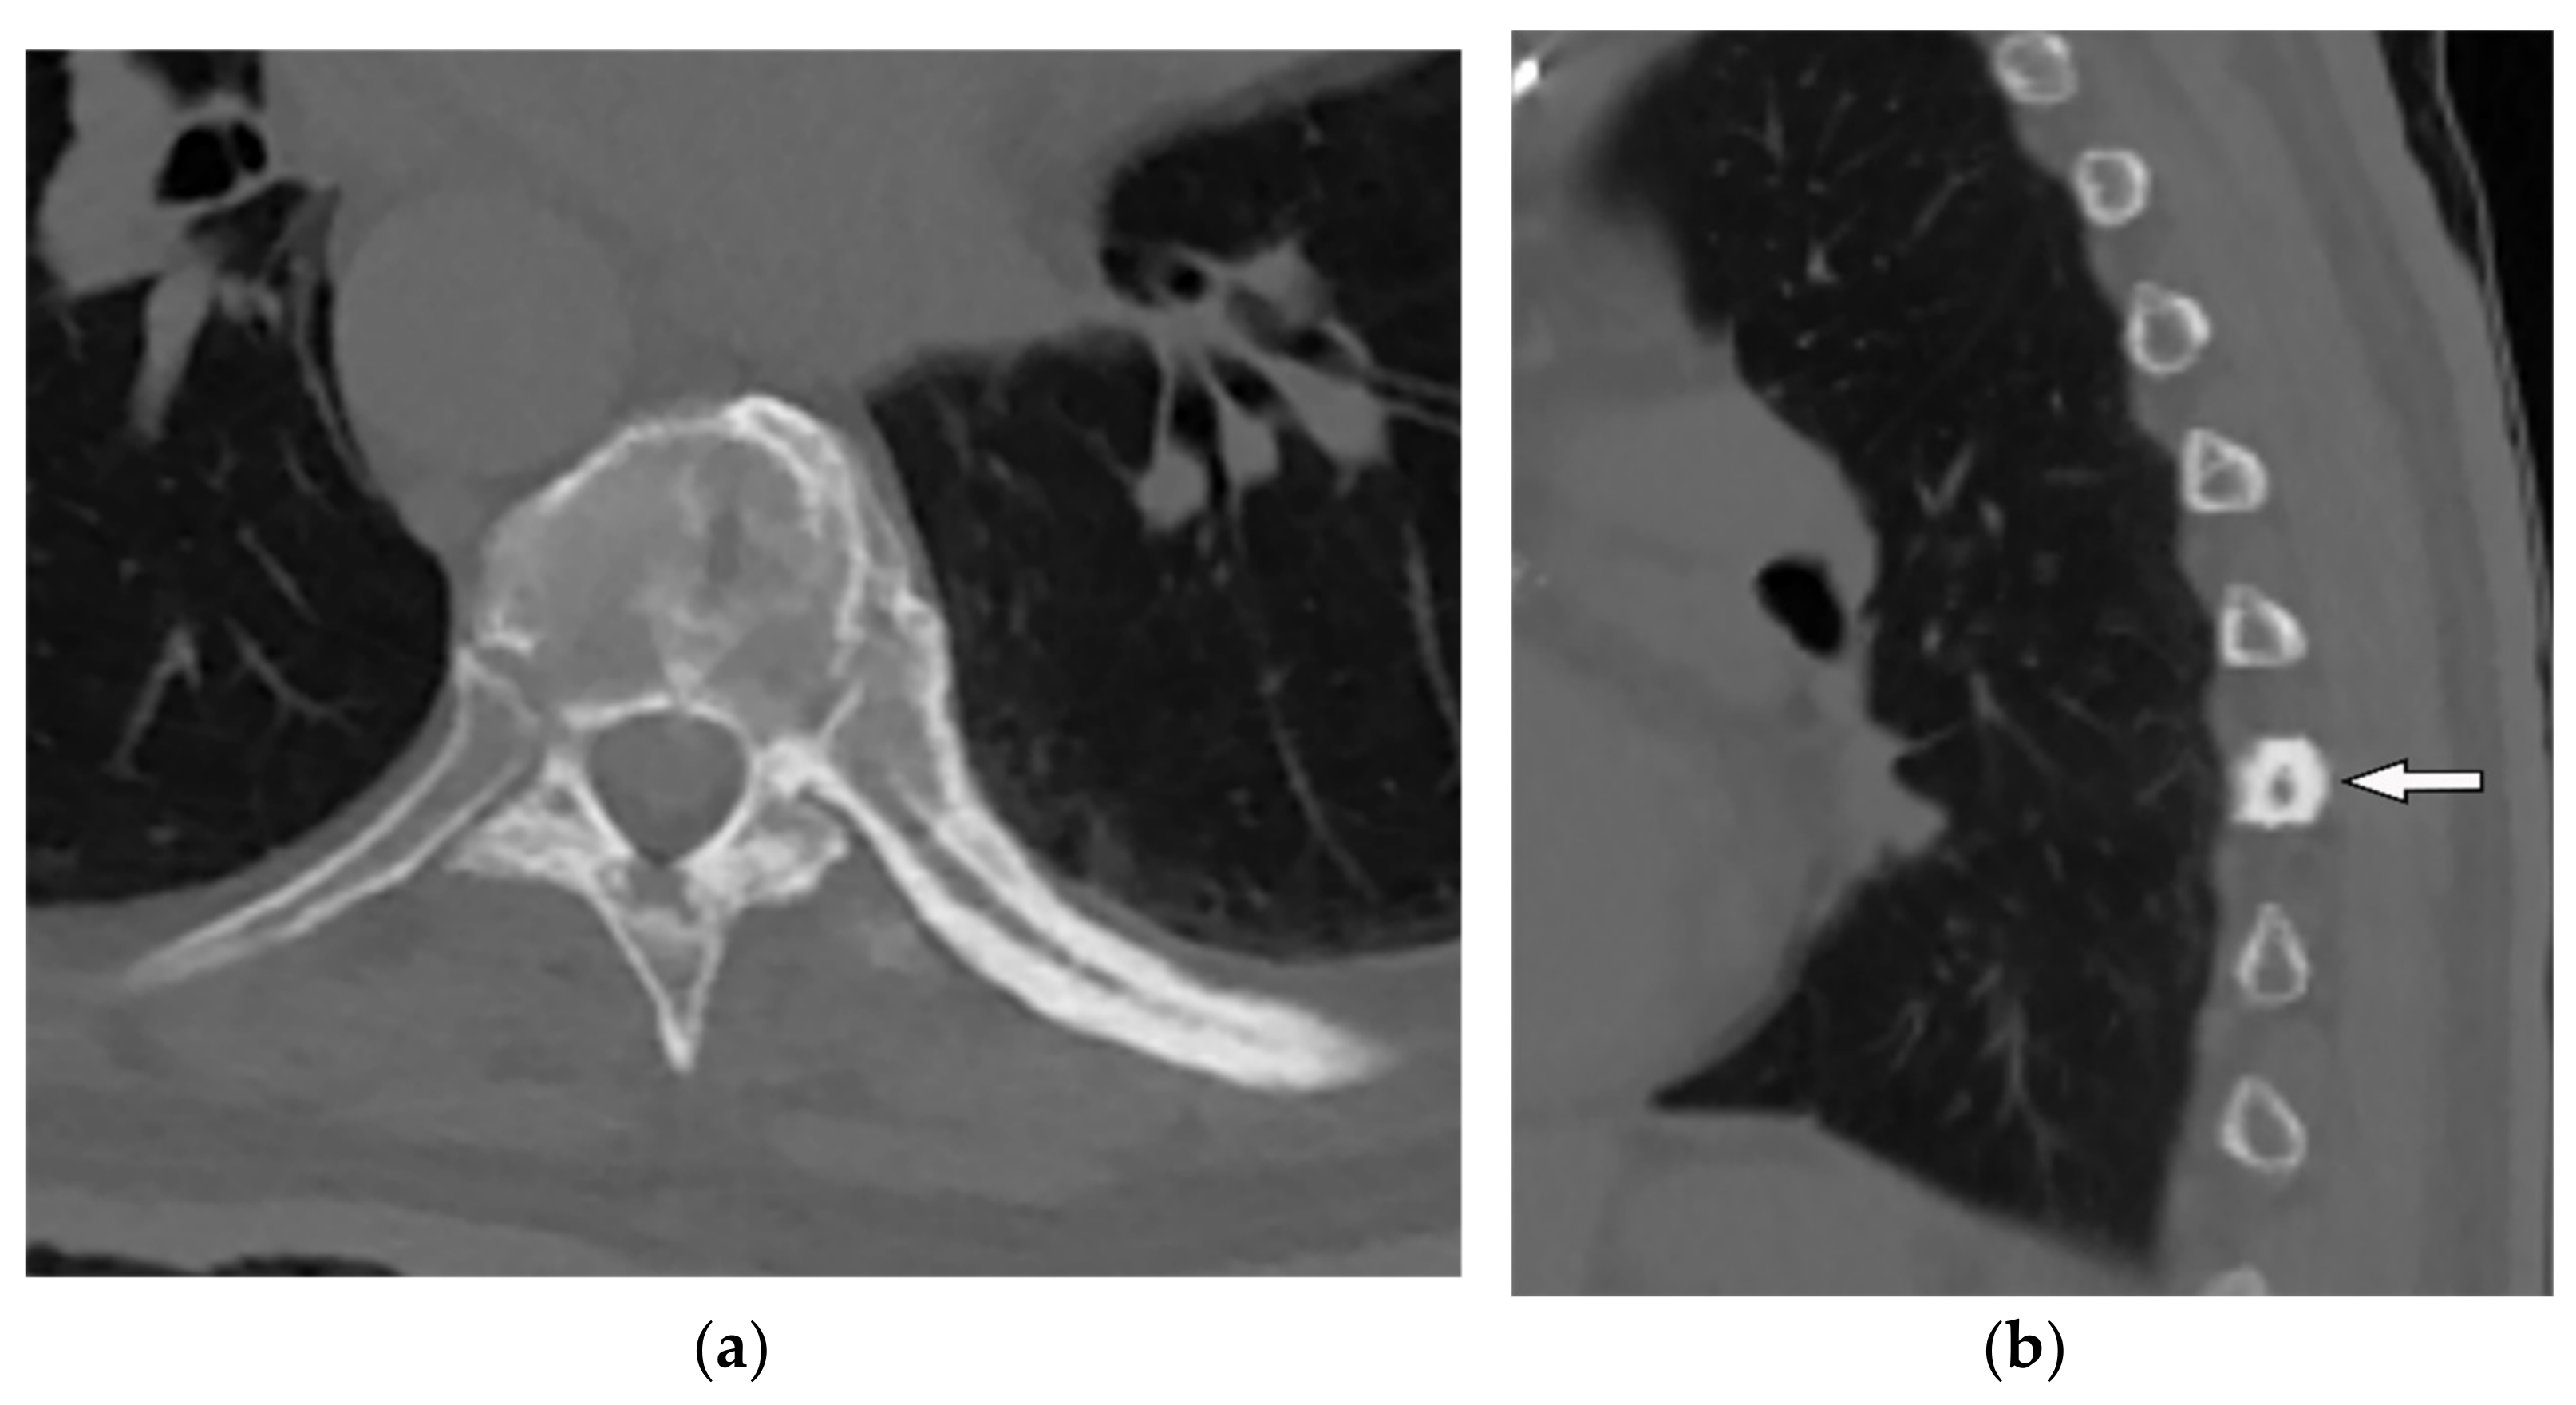

| Osteosarcoma | Dense central calcification, expansile bone remodeling, periosteal reaction, pathologic fracture Sparing of the intervertebral disk while decreasing the height of the vertebral body Lung and nodal metastasis | T1W: low to intermediate signal (high signal in hemorrhage) T2W: hyperintense Mineralization: hypointense on both T1W and T2W T1W FS + C: heterogeneous enhancement |

| Ewing sarcoma | Lytic bone destruction with ill-defined border, rare calcification, heterogenous paraspinal soft tissue with soft tissue larger than osseous component | T1W: iso to hyperintense to the muscle (high signal in hemorrhage) T2W: heterogeneous to hyperintense T1W FS + C: intense homogenous or heterogeneous enhancement |